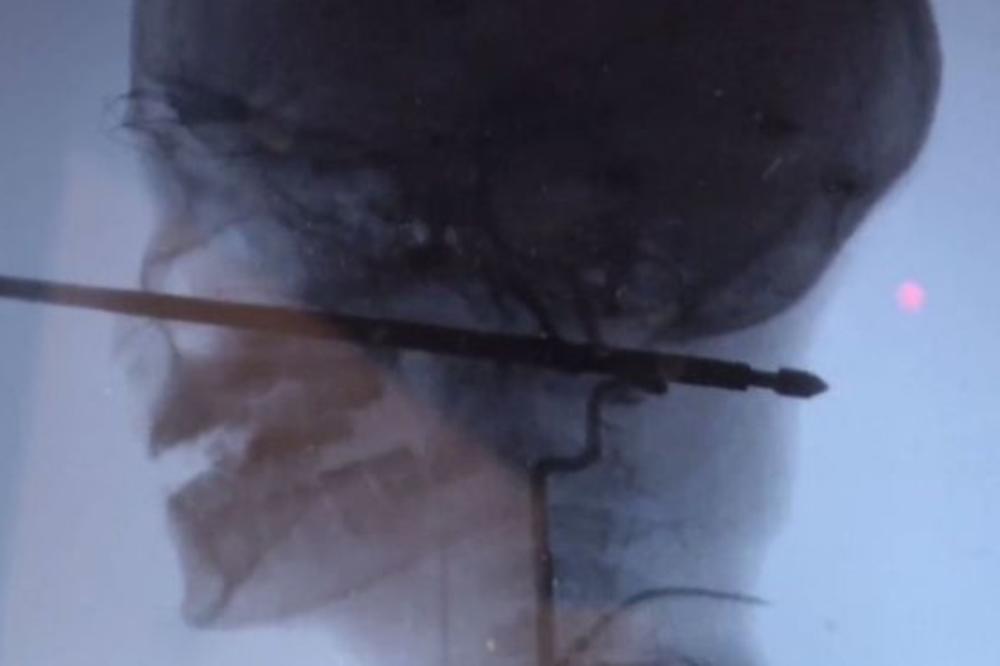

Debela šipka prošla je kroz glavu Ksavijera Kaningema, i promašila je njegove oči, mozak, kičmenu moždinu i sve važnije krvne sudove!

Lekari su nekoliko sati izvlačili četvrtasku šipku iz dečakove glave.

Ksavijer je bio u svom dvorištu u kućici na drvetu, kada su osice počele da ga ujedaju. Braneći se, pao je sa visine pravo na ražanj, koji se zario 15 centimetara u njegovu glavu.

- Ne biste ni nacrtali ovo bolje. Šanse su jedan u milion da ražanj prođe kroz lice u lobanju i ne pogodi sve vitalne stvari.

On je naglasio da je najteže bilo izvući ražanj iz dečakovog vrata, jer je tu najosetljivije mesto.